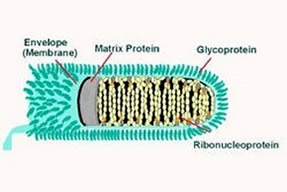

For many years Distemper has been the most feared of all canine diseases possibly only surpassed by Parvo today. Not only does Canine Distemper affect dogs but it affects other animals such as ferrets, seals, mink, weasels and their kin among the Mustelidae family as well as raccoons, pandas and other members of the Procyonidae family. It has even been thought to have been the cause of the deaths of a number of African Lions. Distemper is an RNA virus from the same viral family that causes measles in humans. Although from the same family, distemper is not transmittable to humans. Although contracted by puppies, dogs of all ages are susceptible. Diagnosing distemper can be difficult as it has many of the same symptoms as other illnesses. Some signs of distemper are transient fever, loss of appetite and mild depression as symptoms at the onset. Other dogs are affected by a systemic illness with nasal and ocular discharges, coughing, vomiting and diarrhea. Seizures, behavioral changes, walking in circles and other ambulatory problems commonly develop. Many dogs who show neurological signs develop what is scientifically known as chorea - rhythmic motions or "tics". Dogs that survive both the initial infection and subsequent neurological disease may go on to develop retinal damage, corneal discoloration or extreme hardness of the skin of the nose or foot pads and sometimes even a lifetime of seizures. Currently there is no cure for distemper. The only thing that can be done is supportive care and control of neurological signs. Often times when a dog is diagnosed with distemper it is advised that it be euthanized due to the lifetime of illnesses that they face. Because distemper is present in every bodily excretion and can be spread from contact, human to animal transmission and even through airborne transmission, it is critical that puppies be vaccinated to prevent infection from occurring. Vaccinations should begin at approximately 6 weeks. Because the mother’s milk often interferes with vaccination potency, a regular interval of shots should be given after the first dose and around week 9, 12, 16 and annually thereafter. Doing this will help insure that the dog receives the full value of the vaccination and is of minimal risk to contraction throughout its life.

longer it takes to recognize that your dog is in progressive Parvo, the more drastic the maintenance procedure in keeping them alive and many times the more costly. Distemper, which was first discovered in the early 1900’s, is a very infectious disease that causes death in 50% - 80% of all dogs that are infected. The younger the dog, the greater the chance of death.

Distemper, which was first discovered in the early 1900’s, is a very infectious disease that causes death in 50% - 80% of all dogs that are infected. The younger the dog, the greater the chance of death. Hip Dysplasia is a debilitating disease that is similar in nature to human arthritis. This disease tends to be primarily genetic in nature and affects mostly large breeds of dogs. Although other animals besides dogs can also have this disease.